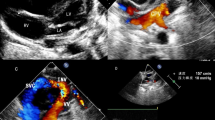

The common characteristics of fetal TAPVC in this study were a smaller left atrium in the 4-chamber view, no PV opening in the posterior wall of the left atrium, and extra vessels behind the left atrium in the 3-vessel trachea view. Modified cardiovascular casts were used in the postpartum diagnosis of 3 TAPVC cases, including 1 case of supracardiac and 2 of infracardiac TAPVC. For cardiac TAPVC, right atrial isomerism, a single atrium and ventricle, double-outlet single ventricle, pulmonary artery stenosis, right aortic arch with mirror branches, right descending aorta, slim ductus arteriosus, and dextrocardia were prenatally diagnosed (case 1, Fig. 1), which was confirmed by postpartum findings (Figs. 2, 3, 4). In the 2 cases of cardiac TAPVC, right atrial isomerism, diaphragmatic hernia, a single atrium, pulmonary atresia, abnormal inflow and atrial isomerism syndrome, levoversion, atrial septal defect, functional single ventricle, double-outlet single ventricle, and double-inlet single ventricle were prenatally diagnosed (case 8, Fig. 5; case 17, Fig. 6), which was confirmed postpartum (Figs. 7, 8, 9, 10, 11).

Prenatal ultrasound diagnosis of fetal supracardiac TAPVC with complex malformations. (A) The common PV trunk was visible in the cross section of the atrium, and posterior left atrium index was increased. (B) Vertical venous return to the left superior vena cava. (C, D) Superior and inferior vena cava return to a single atrium. (E, F) Two- and 3-dimensional flow imaging revealed both the aorta and pulmonary artery originating from a single ventricle with pulmonary stenosis. DAO descending aorta, L left, LPA left pulmonary artery, R right, RPA right pulmonary artery, SA single atrium, SV single ventricle.

Prenatal ultrasound diagnosis of fetal supracardiac TAPVC with complex malformations. (A, B) Two-dimensional and color Doppler flow imaging showed the left and right PVs converging to form a common PV trunk, with an increased posterior left atrium index. (C, D) The common PV trunk returned to the right superior vena cava via the vertical vein in the view showing 3 vessels and trachea. (E, F) Aorta and pulmonary artery originating from a single ventricle. LINV left innominate vein, SP spine, SVC superior vena cava, T trachea, VV vertical vein.

Prenatal ultrasound diagnosis of fetal infracardiac TAPVC with complex malformations. (A, B) Two-dimensional and color Doppler flow imaging showing a single atrium, single atrioventricular valve, single ventricle, and left and right PVs forming a common PV trunk, accompanied by increased posterior left atrium index. The pulmonary artery and aorta both originated from a single ventricle and pulmonary atresia was observed. (C, D) A collateral blood supply from the descending aorta in both lungs was seen in the cross section of the heart. (E) Both left and right atrial appendages were anatomically right atrial appendages. (F) Left and right main bronchi were symmetrical.

Postnatal anatomic and cardiovascular cast findings. (A, B) The prenatal examination revealed a single ventricle, pulmonary atresia, left and right collateral arteries from the descending aorta supplying both lungs, left and right PVs converging to form a PV trunk and descending into the portal vein via the vertical vein.